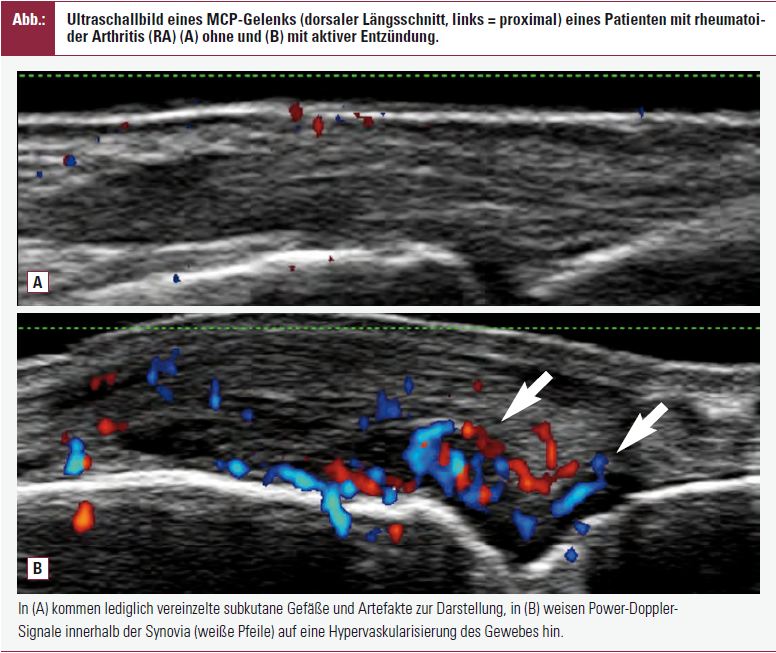

In dieser beim EULAR vorgestellten retrospektiven Analyse von 149 RA-Patienten wurde die Relevanz klinischer Routineparameter zur Unterscheidung ultraschalldefinierter Remission (= Fehlen von Power-Doppler-Signalen [PD-Signalen] in der Synovia) und aktiver Erkrankung (definiert als ≥ 1 PD-Signal) untersucht. Bei allen Patienten wurden systematisch klinische und serologische Parameter erhoben und eine Sonographie der Handgelenke, MCP- und PIP-Gelenke (= 22 Gelenke pro Patient) durchgeführt.